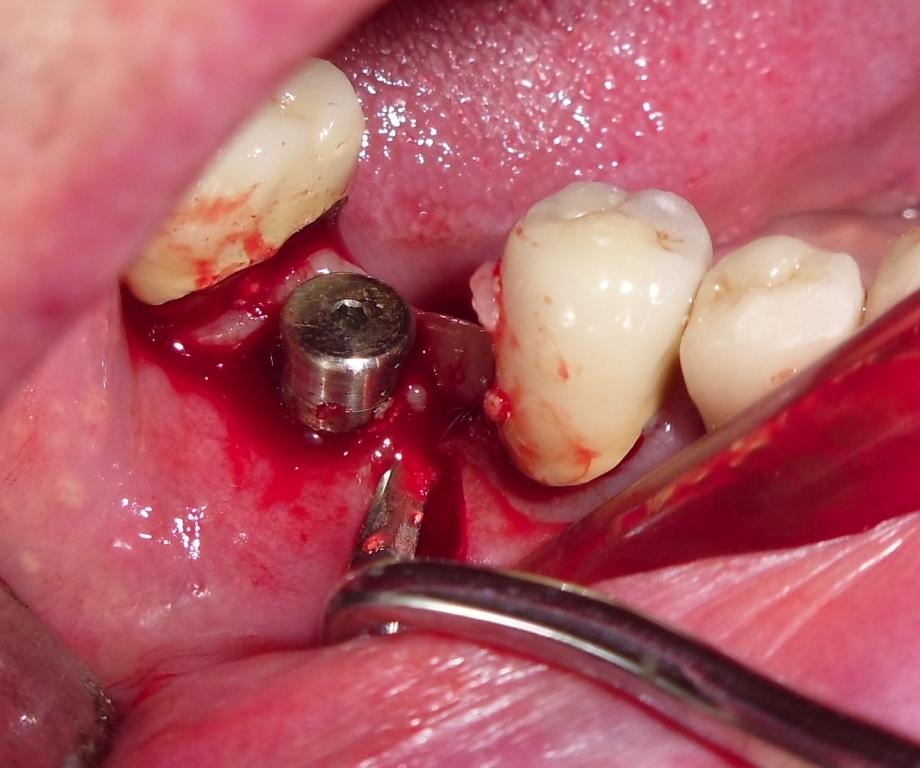

Il giorno dell' intervento le condizioni di igiene orale sono sicuramente migliorate pur non raggiungendo ancora livelli ottimali.

Accesso mediante lembo mucoperiosteo: